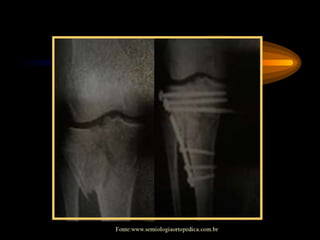

Sinal da Dragona

Fonte:www.semiologiaortopedica.com.br